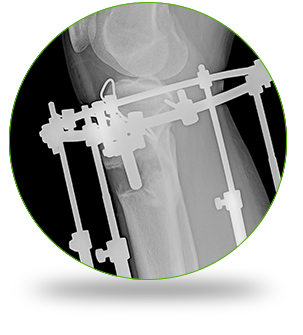

Анон, думал ли ты об увеличении роста апаратом Иллизарова? Я карлан 170, хочу хотя бы 180, а то буду

image.png

>легче шлюху снять дегрод ебаный

Аноним 24/02/26 Втр 01:02:34 #20 №330107002

>>330106979